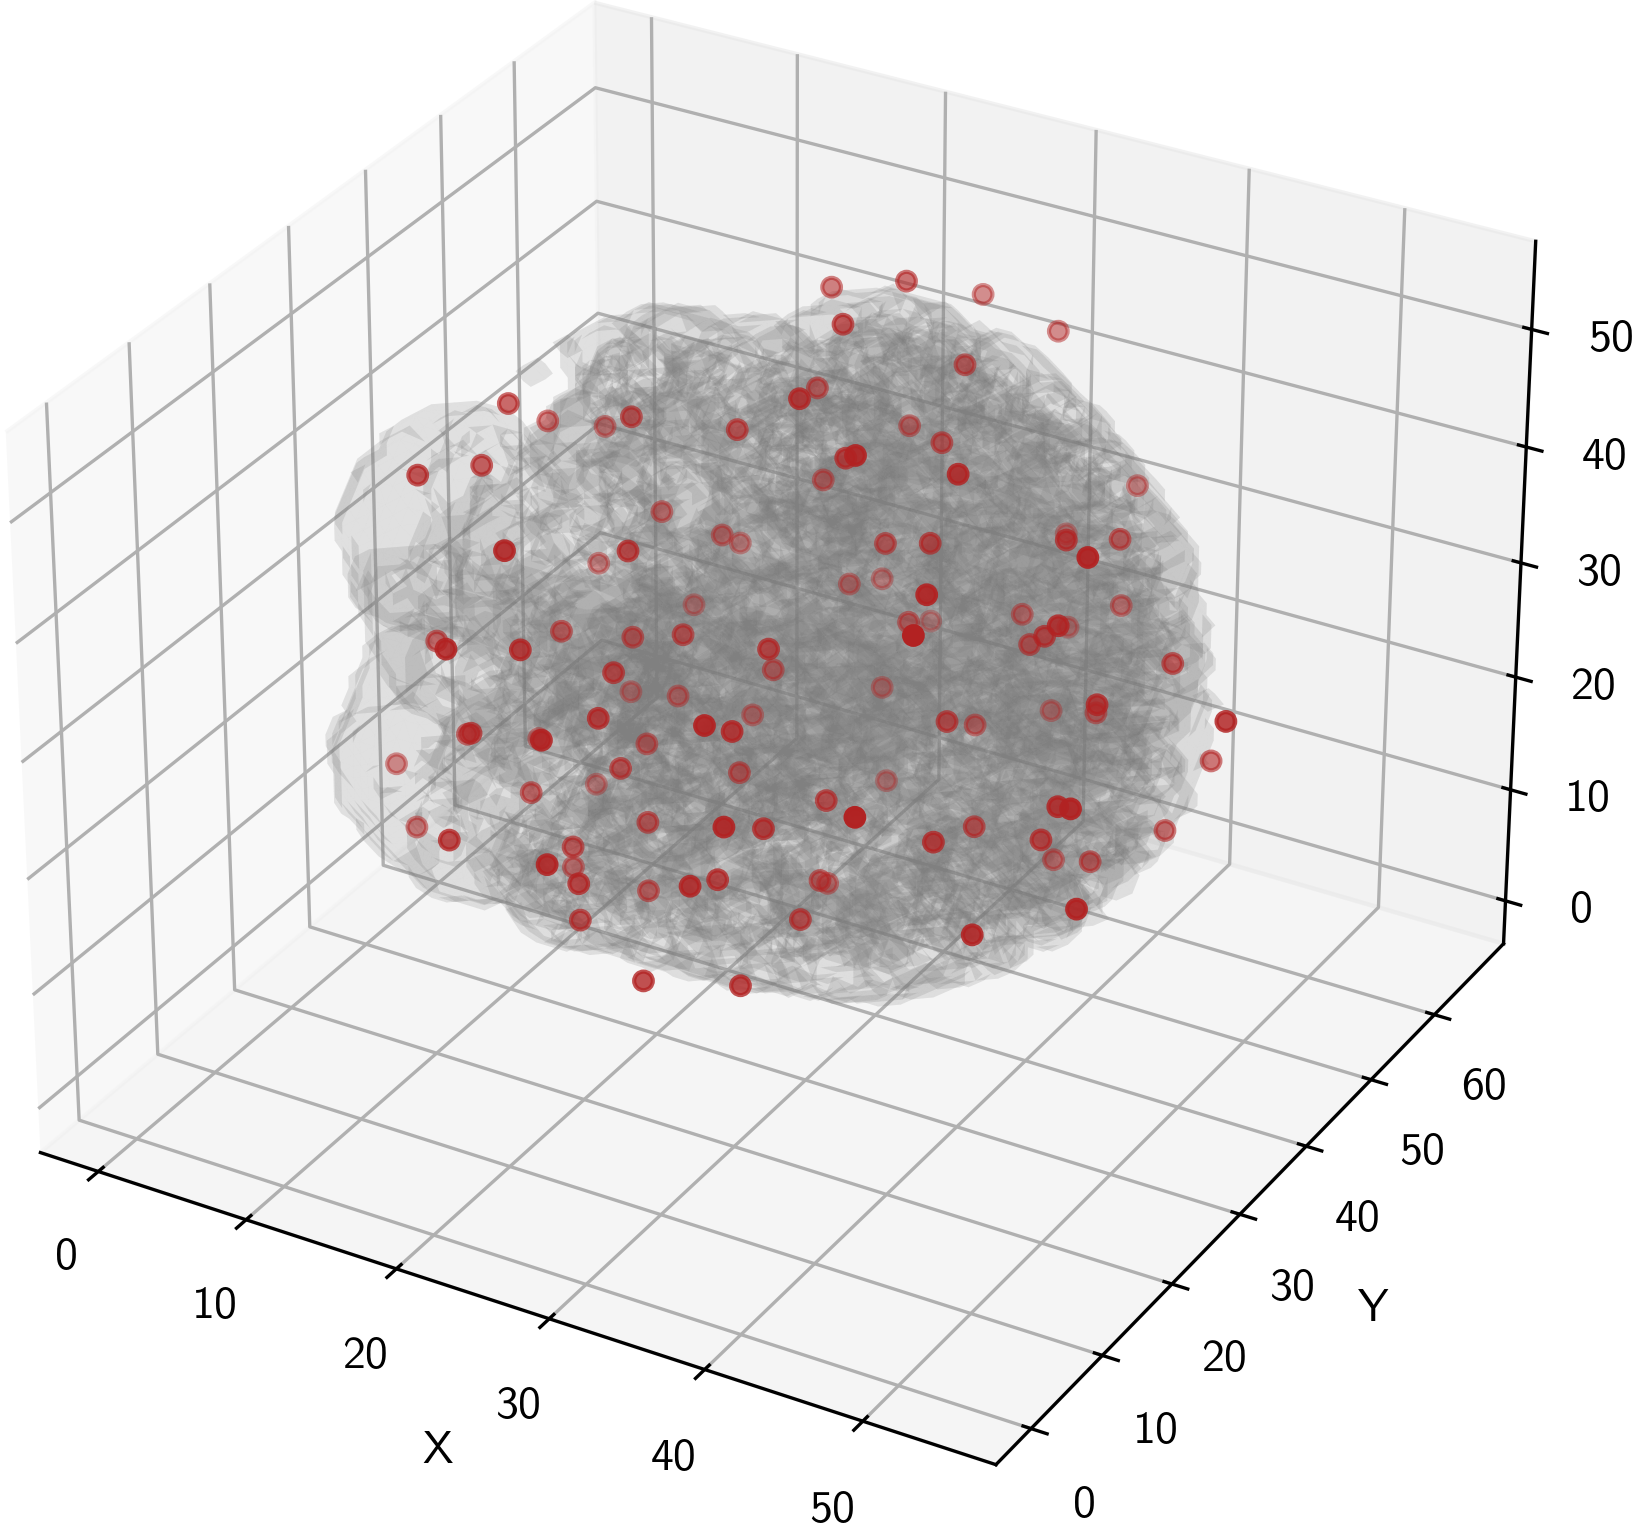

This approach, while reasonably effective, limits models in terms of flexibility and adaptability because the same grid is used for every subject in a dataset, imposing a structural bias and a disregard for individual specificity, as a subject may have functionally distinct regions that do not align well with predefined anchor patches. Additionally, selecting anchor patches in this ROI, grid-based manner poses the risk of many patch centers falling outside of the GM region of the brain (as demonstrated in Fig. 3(a). For FCA, this poses a problem, as the goal should be to extract the most functionally relevant patches from the GM.

Our randomized approach to anchor selection fixes this (see Fig. 3)(b), offering anchor patches that are more diverse across patients, as well as more conformed to brain anatomy. This ensures that more functionally relevant patches are extracted from the anchor regions. The better anatomical conformity is validated by Fig. 4. As seen, our proposed anchor selection approach produces anchor patches whose centers are 45.32% closer to the GM boundary compared to those produced by the baseline approach.